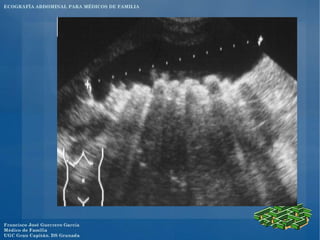

El documento presenta un programa de ecografía abdominal para médicos de familia que incluye presentaciones sobre generalidades de la ecografía y anatomía normal de los órganos abdominales los jueves, y sobre imágenes anormales en ecografía abdominal y ecografía obstétrica los viernes, con un caso clínico el sábado en el centro.